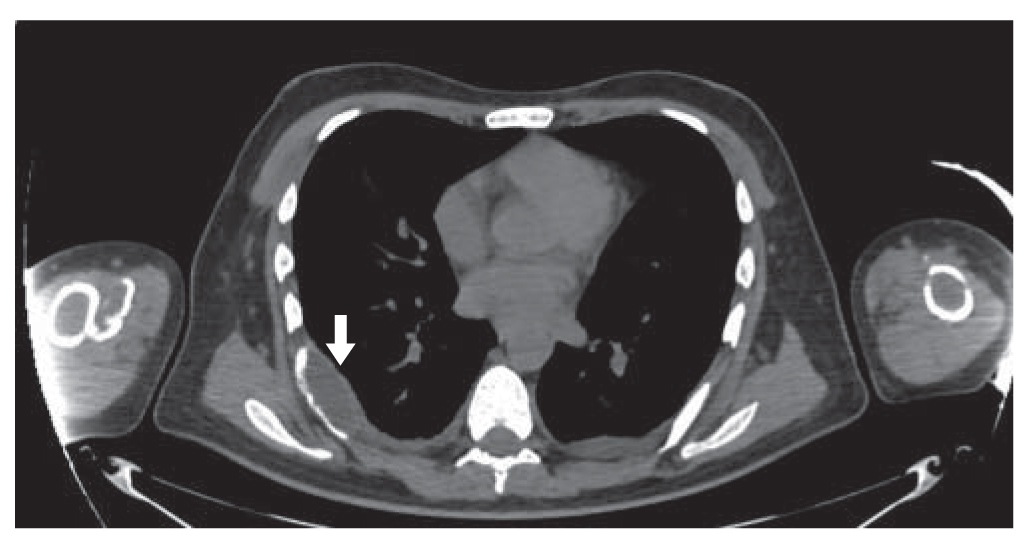

На третьи-четвертые сутки с момента операции отмечено появление субфебрильной лихорадки к вечеру с подъемом на пятые сутки до фебрильной. В общем анализе крови – увеличение СОЭ до 31 мм/ч без признаков лейкоцитоза. В общем анализе мочи – лейкоцитурия до 29 в п/зрения. Проведена МСКТ органов грудной полости, органов брюшной полости и забрюшинного пространства с выявлением КТ-картины псевдомембранозного (?) колита, мезентериальной количественной лимфаденопатии, гиповентиляции в нижних долях легких и незначительного количества жидкости в плевральных полостях. Визуализированы повторно множественные конкременты в чашечках почек (рис. 1) и конкремент в мочевом пузыре, множественные образования костей (бурые опухоли, рис. 2), с наличием патологических переломов левой и правой плечевых костей (рис. 3). Отмечены послеоперационные изменения – неоднородность мягких тканей шеи с наличием включений газа и жидкости слева. Проводилась антибактериальная и дезинтоксикационная терапия. В остальном – послеоперационный период без осложнений.

Рис. 1. Конкременты в почках.

1. Рис. 1. Конкременты в почках. | |